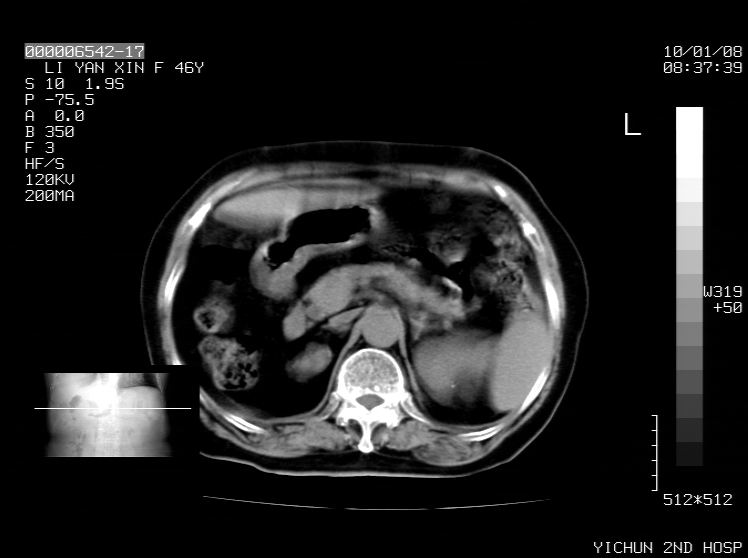

右侧膈膨升,胆囊壁厚,右侧肾脏缺如。病史?

右侧膈膨升,肝内钙化灶,胆囊壁厚,右侧肾脏缺如。病史?

右膈膨出,肝脏变异,肝内钙化,右肾缺如,脾大。

右侧膈膨升,肝内胆管结石?

右侧膈膨升,胆囊壁厚,右侧肾脏缺如,增强,腔静脉旁是否是移位肾

肝脏变异致膈升高,肝左叶肝内胆管结石.右肾萎缩,左肾代偿肥大.

胆囊ct未见确切异常,请结合b超。右侧肾窝未见确切肾脏影,右肾萎缩?异位?

右侧膈膨升,肝内钙化灶,胆囊壁厚,右肾萎缩或发育不良。